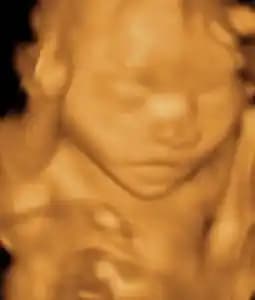

Week 12

Baby is about 2 inches long, and their face is starting to look more defined. They have started to develop their reflexes.